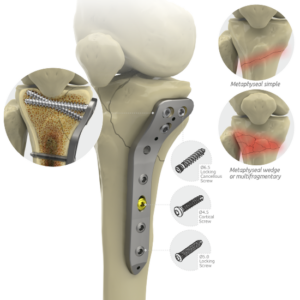

Large Fragment Locking Plate System

Locking Proximal Lateral Femoral Head Plates